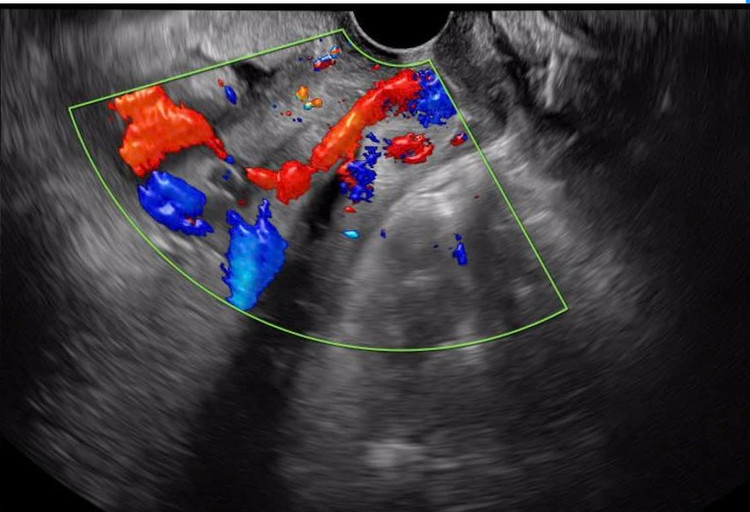

| Rau tiền đạo, mạch máu tiền đạo - Ảnh BVCC |

Mạch máu tiền đạo có thể được chẩn đoán bằng cách siêu âm đầu dò kết hợp với siêu âm Doppler. Bác sĩ khuyến nghị thực hiện siêu âm mạch máu tiền đạo cho các thai phụ có nguy cơ cao đặc biệt các bà mẹ được chẩn đoán có nhau cài răng lược hoặc có các dấu hiệu cảnh báo mắc phải hiện tượng này.